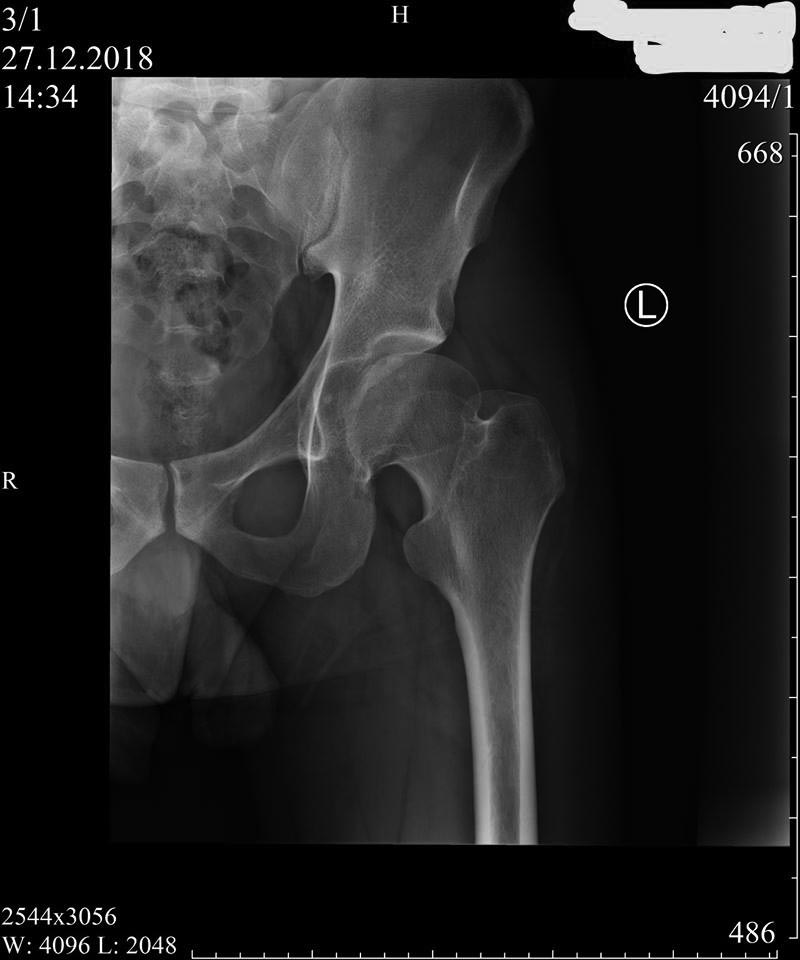

Пациент 27 лет: с 14-ти - "щёлканье" в тазобедренных суставах...

Последние полгода - боль (особенно после вставания из положения сидя),

которая устраняется "встряхиванием" ноги (правой) со "щелчком"...

Владимир Георгиевич Босых (профессор МГМСУ) полагает, что на

рентгенограммах: "ярко выраженный подвывих бедра и в зависимости от

клиники надо ставить вопрос о хирургической коррекции (возможно, тройной

остеотомии таза)".